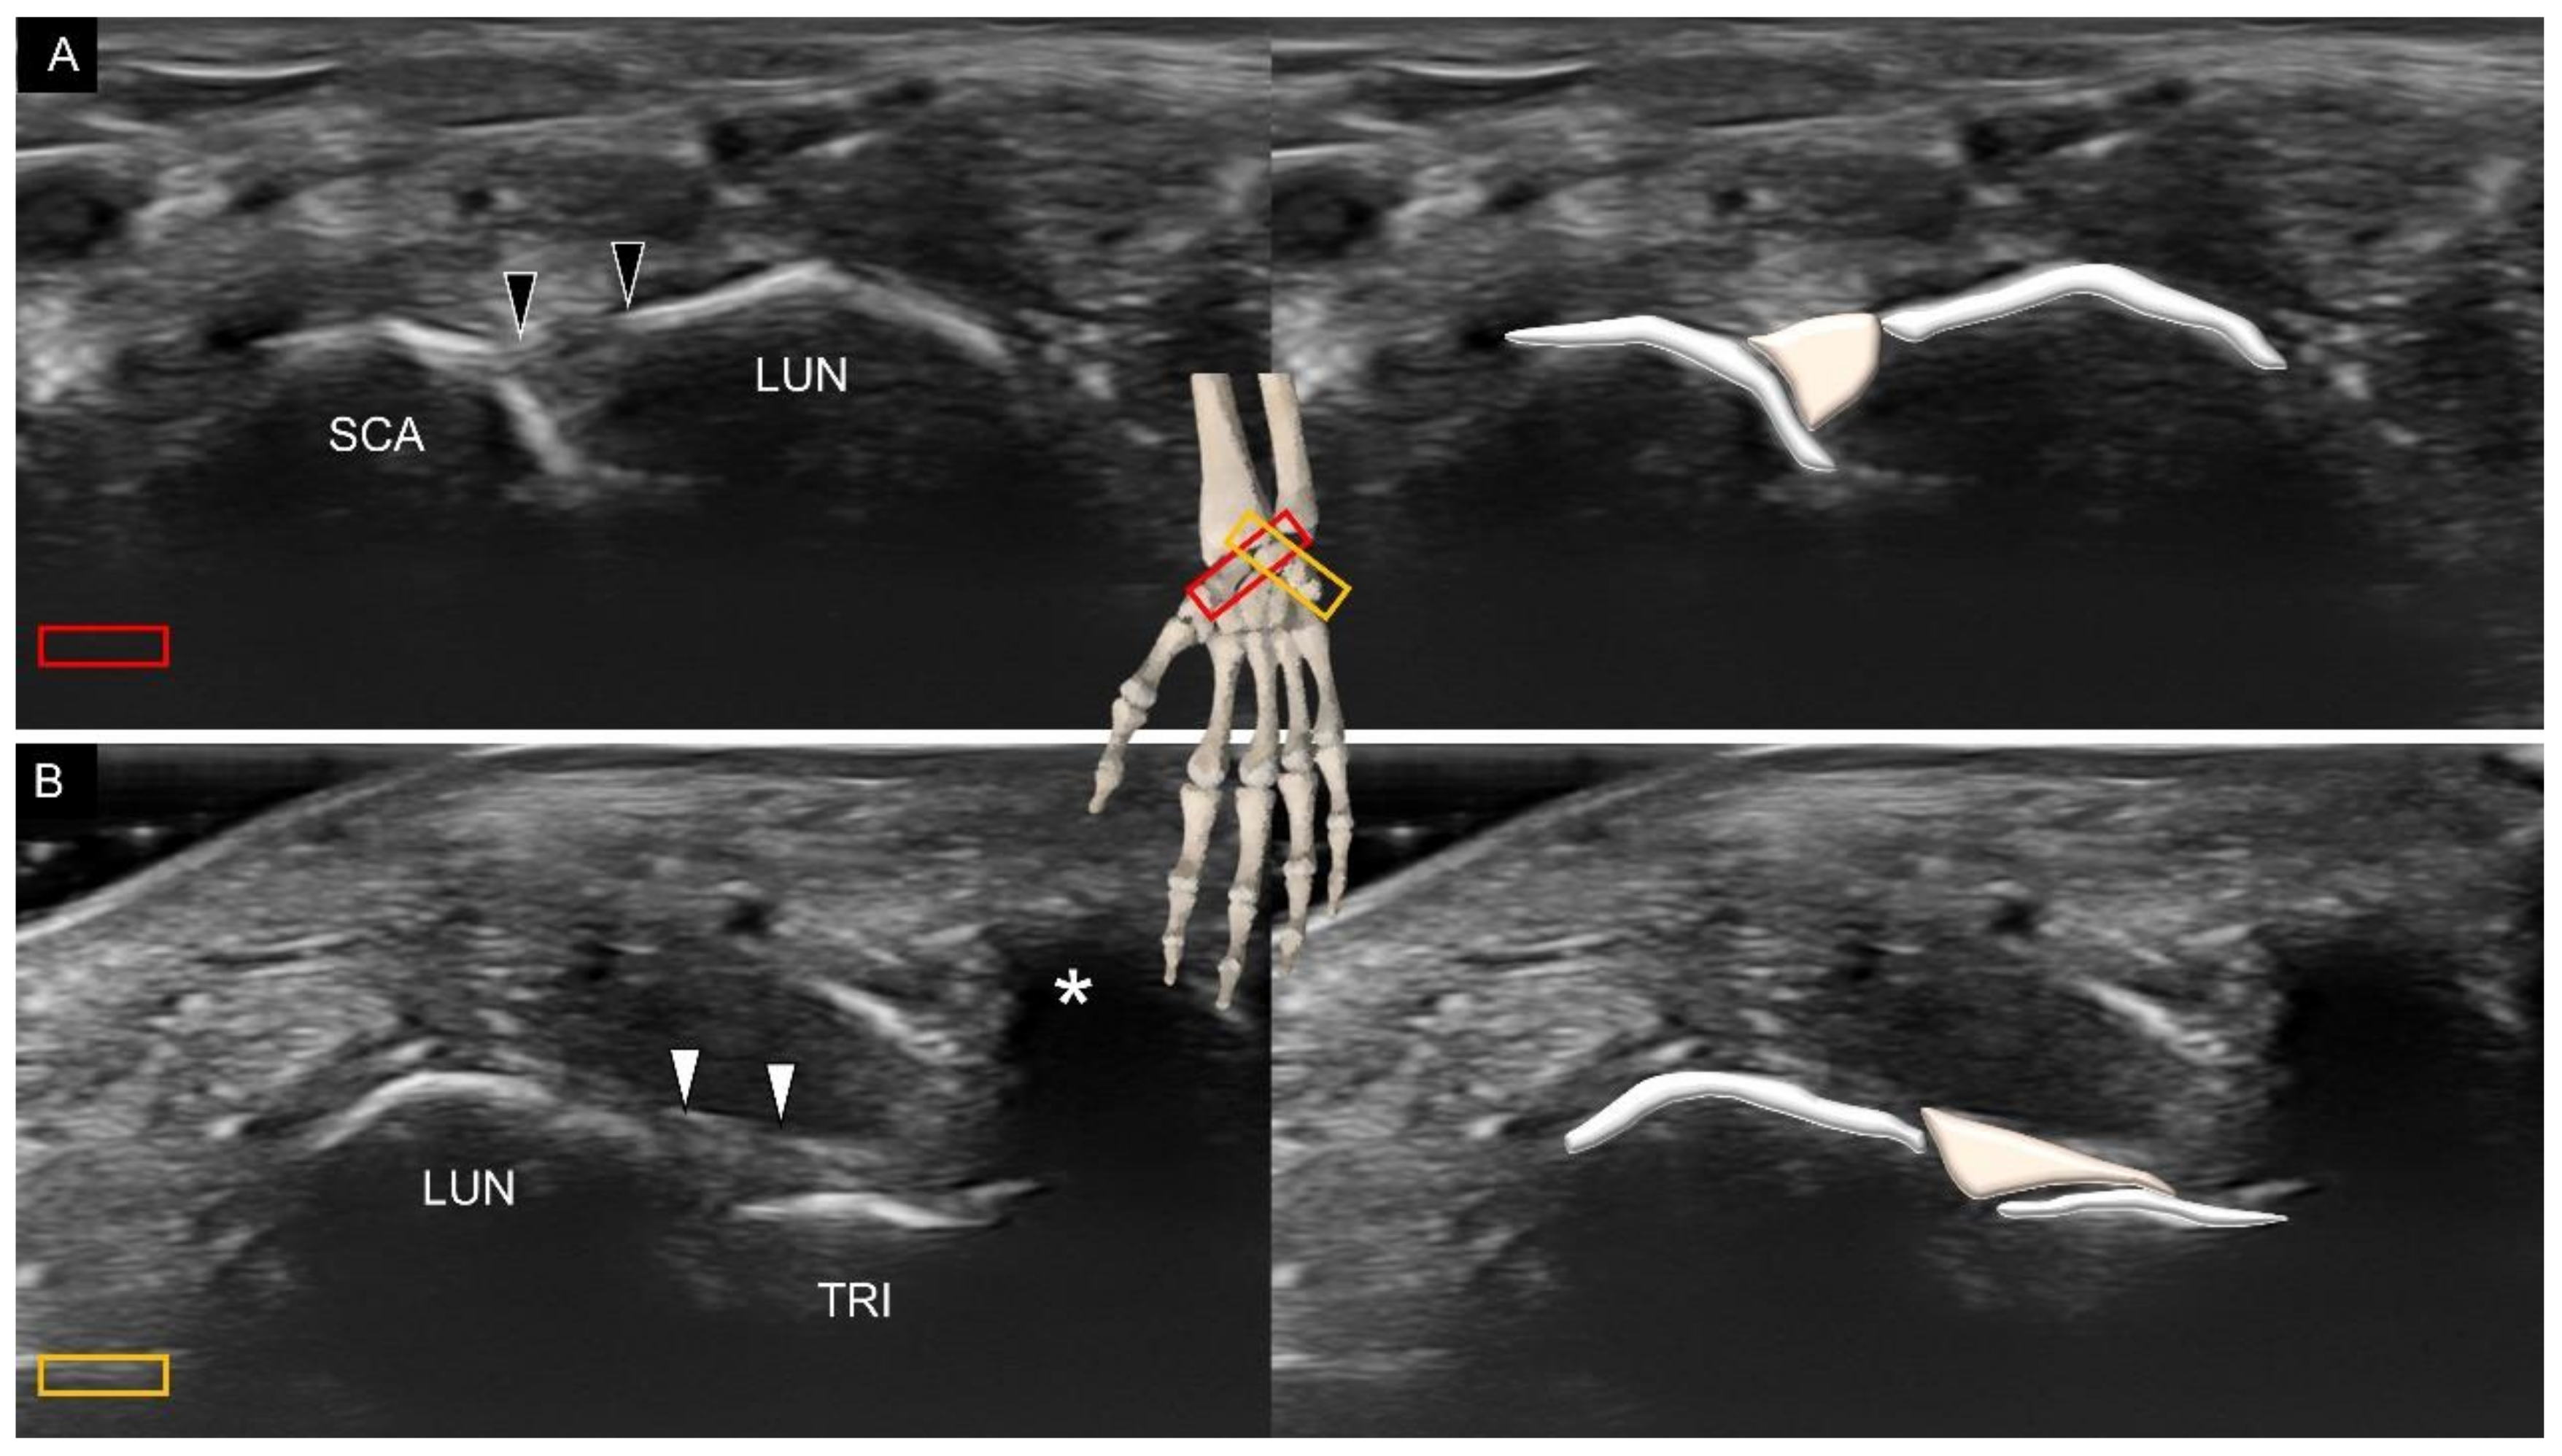

3.2. Attachment to the Lunate

4. Sonoanatomy of Volar Intrinsic Carpal Ligaments

6. Sonoanatomy of Dorsal Intrinsic Carpal Ligaments